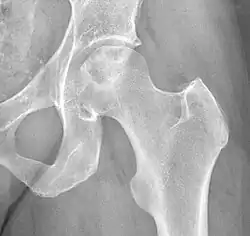

ANFH can only be diagnosed by MRI of the hip and X-rays of the hip specifically in the anteroposterior and frog-leg lateral poses.[2] Along with these scans an additional bone scan needs to be done which allows doctors to see the activities of bone cells in a body. Once the images that the physician want are obtained, they are then measured through two systematic reviews.

| Stage III | X-ray and MRI indicates evidence of subchondral collapse, crescent sign, or flattening of the FH |

| Stage IV | MRI and X -ray show narrowing of the joint space with secondary degenerative changes in the acetabulum, which is the socket portion of the hip that is a part of the pelvis, such as cysts, osteophytes, and cartilage destruction. |